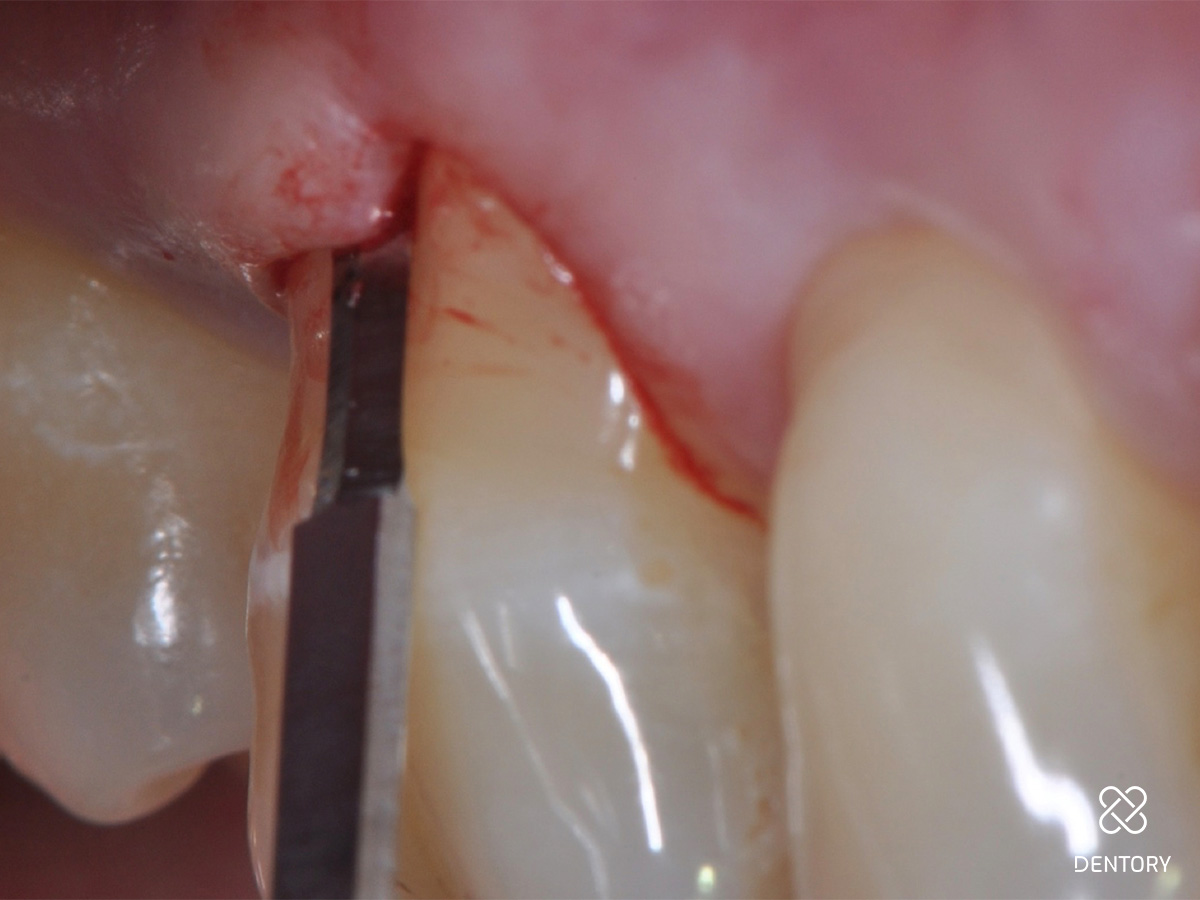

Abbildung 4

Lappenpräparation: Die Lappenpräparation beginnt mit der intrasulkulären Inzision auf den bukkalen Flächen der beiden zum Defekt benachbarten Zähne (16 und 17) mit einer mikrochirurgischen Skalpellklinge. Es werden keine vertikalen Entlastungen durchgeführt. Wenn der Zugang zum knöchernen Defekt nicht ausreicht, kann ein weiterer Nachbarzahn in die Lappenpräparation integriert werden.